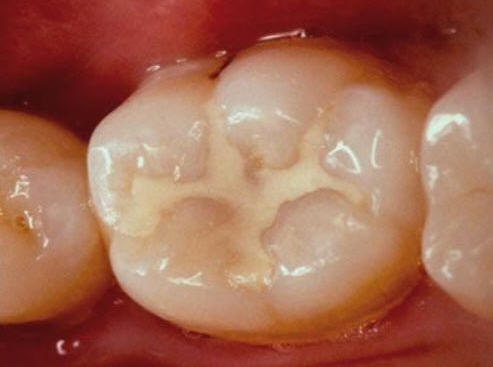

Imagen digital que representa la microfiltración y penetración del sellante realizado.

Microfotografía: Muestra como el sellador obtura la caries subyascente, evitando su avance.

Código 3 (Caries moderada) in vitro. Los códigos 3 in vivo debe ser sellado para evitar el avance del proceso carioso. (MNO)

Código 4 (Caries moderada) in vitro. Los códigos 4 in vivo deben ser tratados en forma operatoria con preservación dental (MOPD), porque presentan dentina infectada.